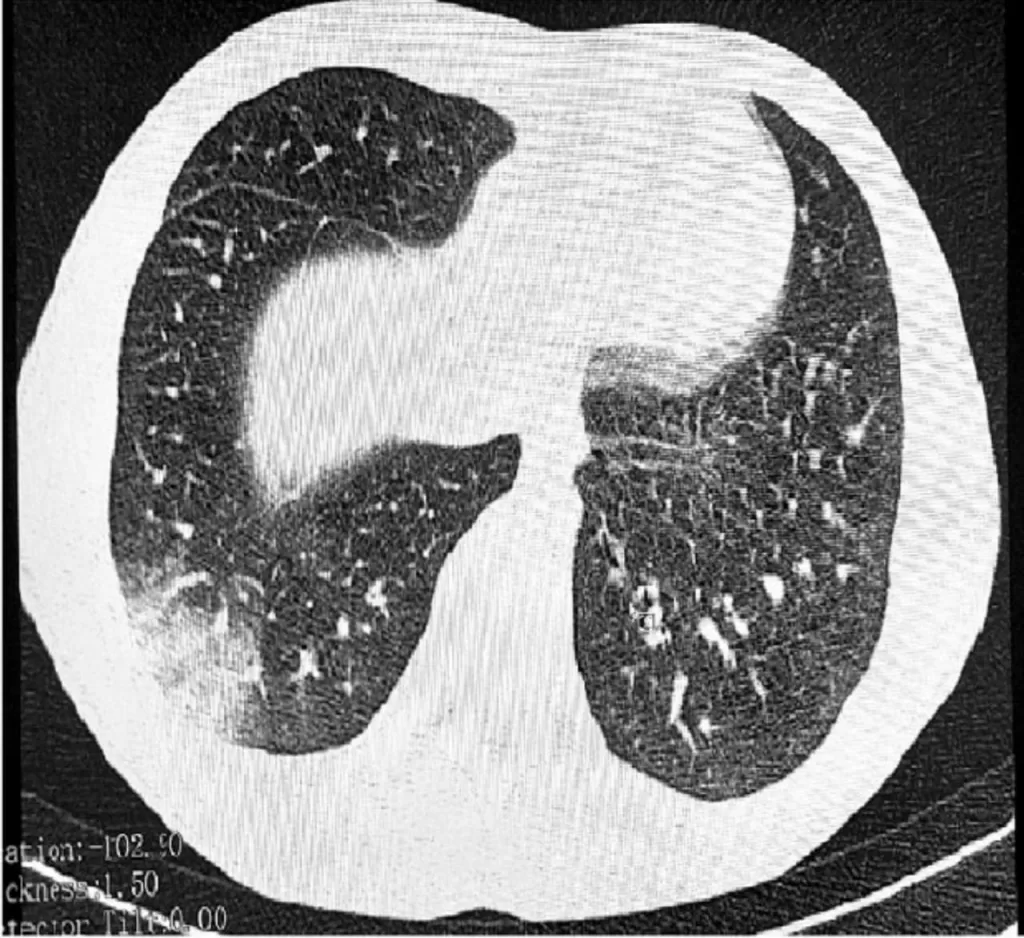

Кроме того, мелкие частицы аэрозоля проникают глубоко в легкие, где они могут накапливаться и вызывать хроническое воспаление. Именно этим объясняется прогрессирующий характер «болезни вейперов».